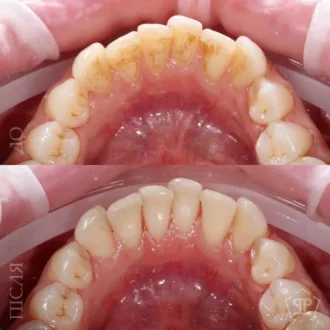

Комплексная гигиена зубов: гигиеническая чистка скейлером + аппаратом Air-Flow + полировка зубов профессиональной пастой